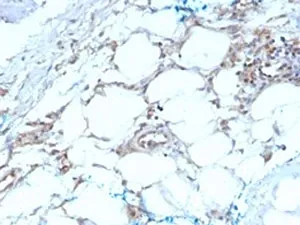

It recognizes a protein of about 29kDa, which is identified as Calretinin (also known as Calbindin 2). Calretinin is a vitamin D-dependent calcium-binding protein involved in calcium signaling. It is present in subsets of neurons throughout the brain and spinal chord, including sensory ganglia. Antibody to calretinin is useful in differentiating mesothelioma from adenocarcinomas of the lung. It also aids in differentiating adrenal cortical neoplasms from pheochromocytomas.UniProt:

IHC-PFormat: